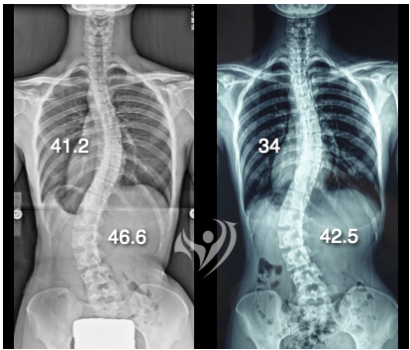

14歲來自香港!3.2週密集訓練改善62.5度胸椎側彎

胸椎62.5度降到55度; 腰椎45.5度降至37度

在治療結束前夕,她的胸椎側彎及腰椎側彎度數均獲得改善,胸椎側彎由62.5度降到55度、腰椎側彎則由45.5度變為37度。